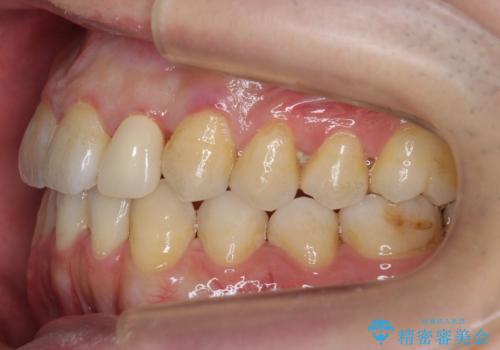

前歯の矮小歯 奥歯の反対咬合 をインビザラインで

- 上下の前歯が気になり来院。

左上2が矮小歯で小さく、また、左の奥歯が反対咬合になっていました。

左上2番はセラミッククラウンで反対側と同じ大きさにしました。

インビザラインでの臼歯の反対咬合の治療は難しいことが多いです。

今回は下の前歯を1本抜くことで、下の奥歯をしっかり内側に傾けて治療を行いました。